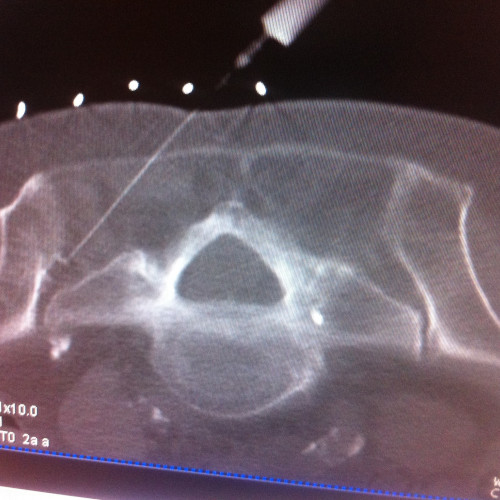

CT-gezielte Infiltrationsbehandlung – Es kann die Nadel millimetergenau an die betroffene Region gebracht werden. Die Strahlenbelastung ist in etwa gleich der röntgengezielten Infiltration mit dem Vorteil der besseren Darstellung der Strukturen. Die CT-gezielte Infiltration wird von mir im Röntgeninstitut „Bellaria Diagnose“ im ersten Wiener Bezirk ambulant durchgeführt.

- CT gezielte Infiltrationen der Facettengelenke, Nervenwurzeln, ISG, epidurale Flutungen caudal und dorsal